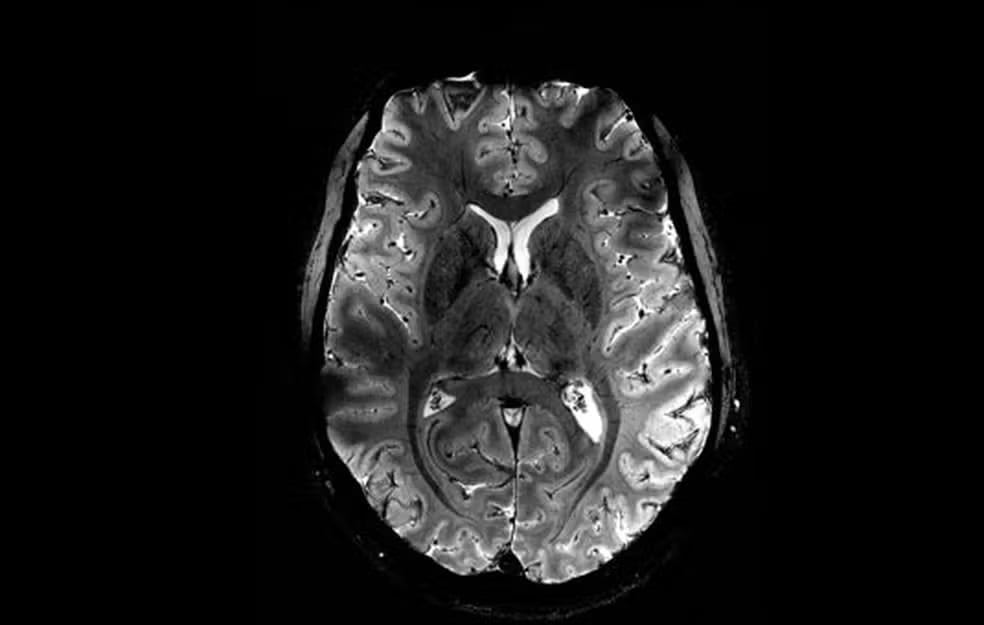

Prepare-se para ser surpreendido! Recentemente, a Comissão Francesa de Energia Atômica e Energia Alternativa (CEA) revelou à imprensa o que seriam as primeiras imagens de um cérebro humano. As mesmas foram capturadas por um scanner de ressonância magnética (RM) de 11,7 Teslas, o mais potente do mundo, lançando luz sobre a anatomia e função do órgão.

Vale destacar que esta máquina pode captar imagens com resolução 10 vezes maior do que os scanners de ressonância tradicionais, chegando a registar microscópicos do cérebro humano em apenas 4 minutos, ou minúsculos vasos sanguíneos que irrigam o córtex cerebral. O nível de precisão é sem precedentes! Impressionante, não?

Só para se ter uma ideia, com os resultados de informações obtidos desse modelo de ressonância, os cientistas podem simular estruturas e funções cerebrais com uma clareza sem precedentes. Pense nas possibilidades de pesquisa!